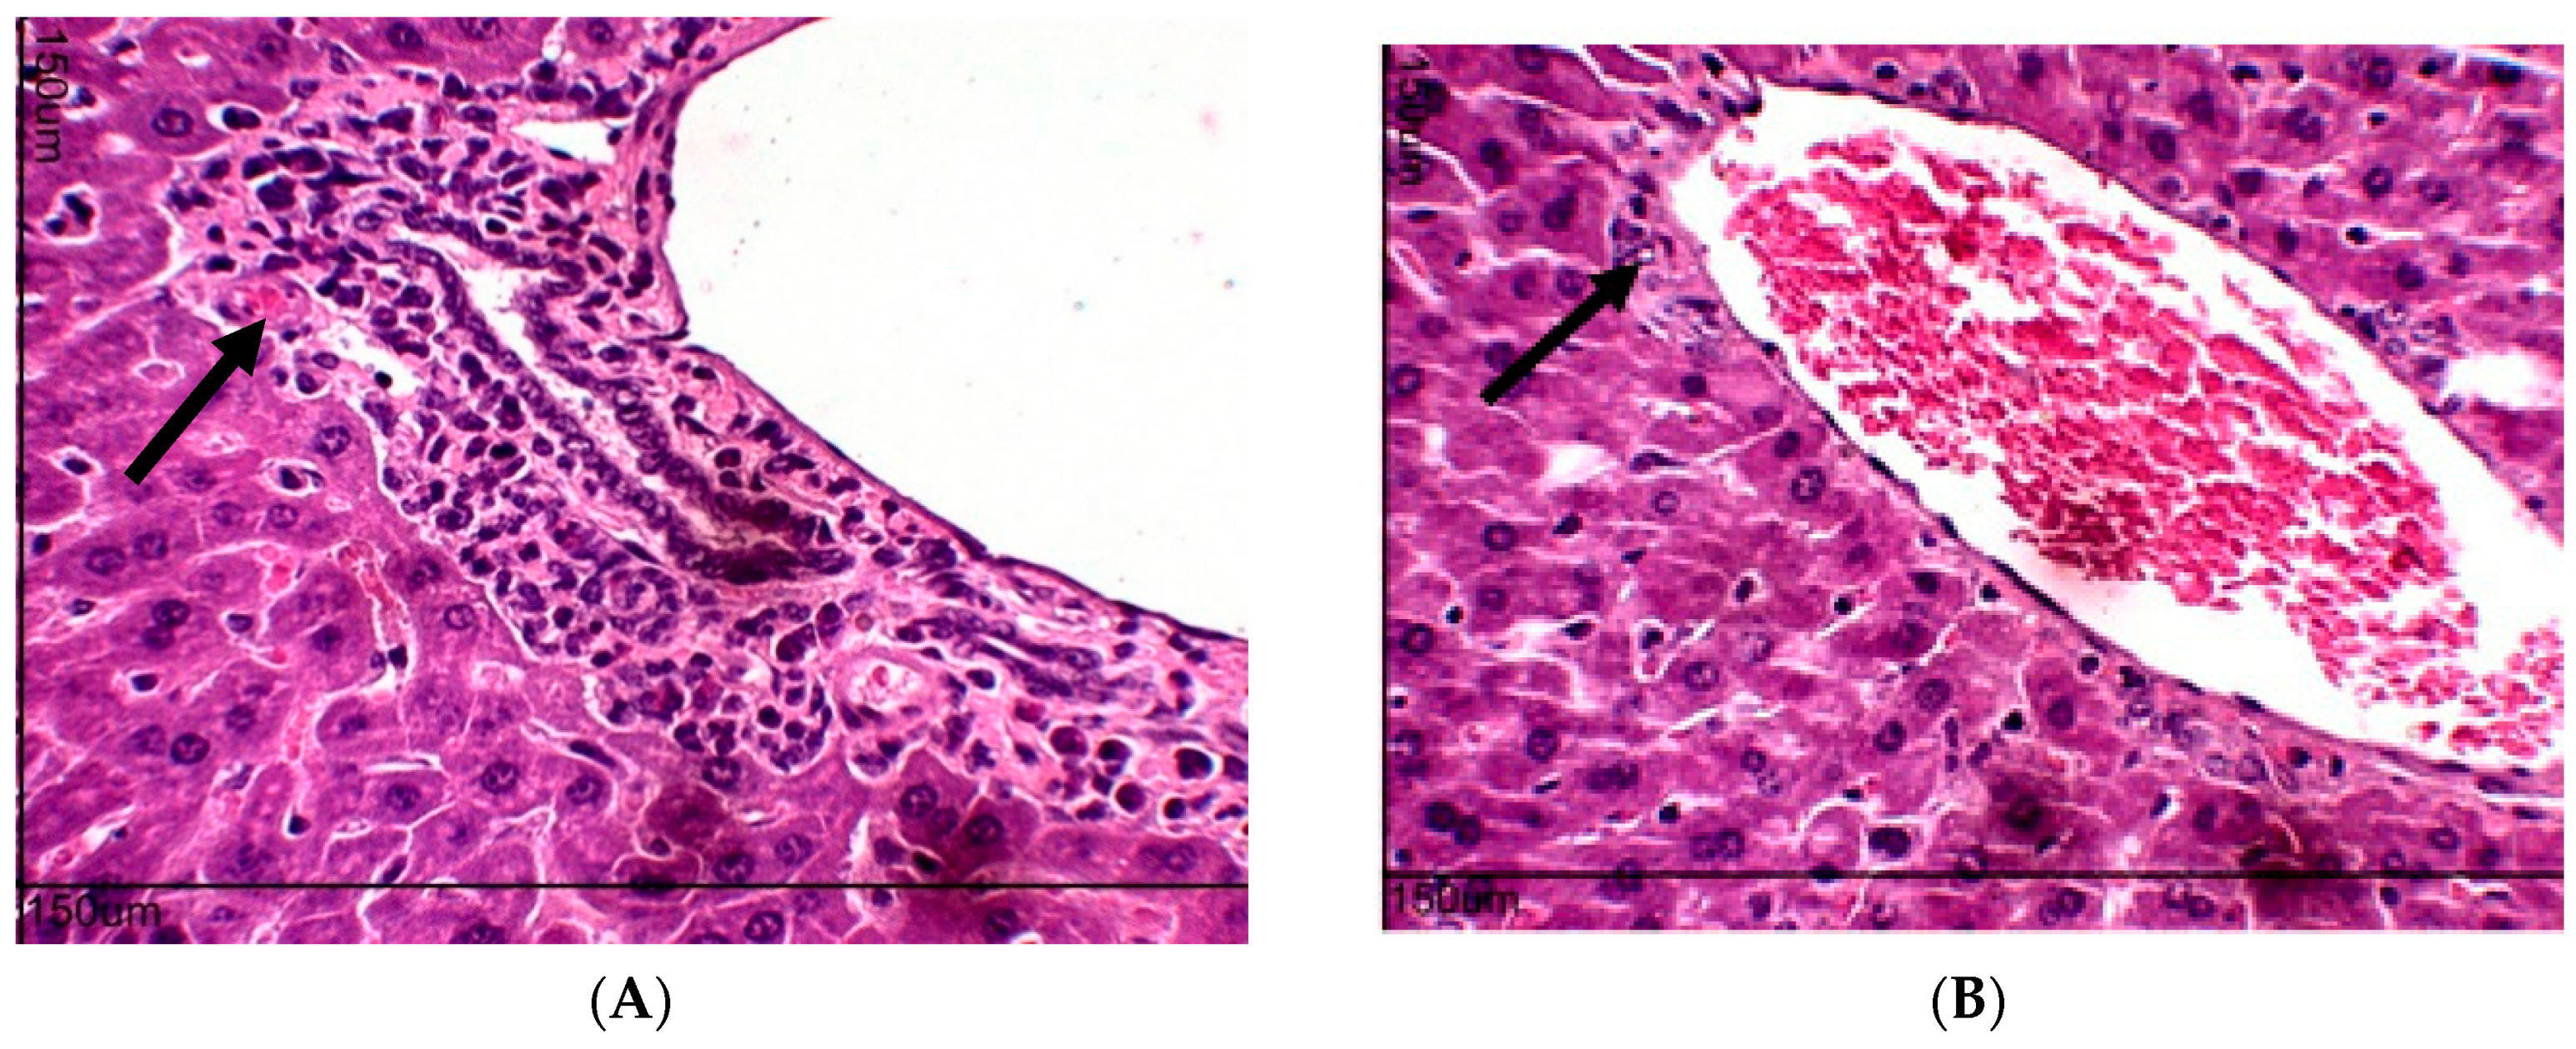

2.7. Quantification of Cytokines in the Peritoneal Lavage

4.5.2. Evaluation of Antiangiogenic Effect